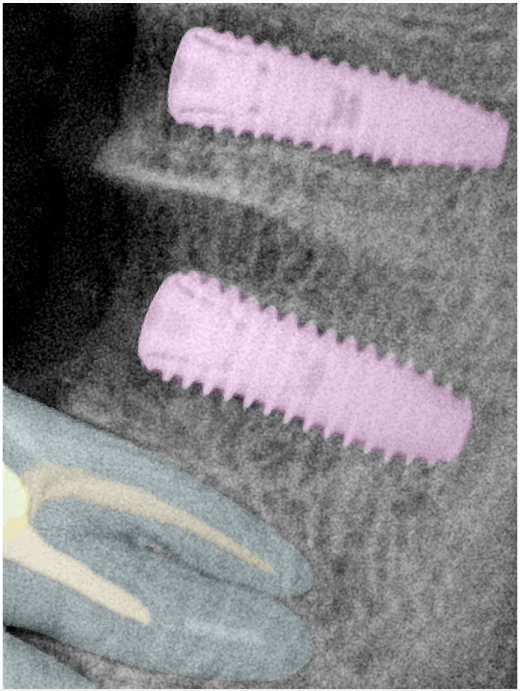

第三版算法分辨率效果比较

| 编号 | 原图 | 第一版 | 第二版 | 第三版 1216x1600 | 第三版 768x1024 | 第三版 1120x1120 |

|---|---|---|---|---|---|---|

| 131315.jpg | ![]() | ![]() | ![]() | ![]() | ![]() | ![]() |

| 131316.jpg | ![]() | ![]() | ![]() | ![]() | ![]() | ![]() |

| 131317.jpg | ![]() | ![]() | ![]() | ![]() | ![]() | ![]() |

| 131318.jpg | ![]() | ![]() | ![]() | ![]() | ![]() | ![]() |

| 131319.jpg | ![]() | ![]() | ![]() | ![]() | ![]() | ![]() |

| 131320.jpg | ![]() | ![]() | ![]() | ![]() | ![]() | ![]() |

| 131321.jpg | ![]() | ![]() | ![]() | ![]() | ![]() | ![]() |

| 131326.jpg | ![]() | ![]() | ![]() | ![]() | ![]() | ![]() |

| 131327.jpg | ![]() | ![]() | ![]() | ![]() | ![]() | ![]() |

| 131328.jpg | ![]() | ![]() | ![]() | ![]() | ![]() | ![]() |

| 131330.jpg | ![]() | ![]() | ![]() | ![]() | ![]() | ![]() |

| 131331.jpg | ![]() | ![]() | ![]() | ![]() | ![]() | ![]() |

| 131332.jpg | ![]() | ![]() | ![]() | ![]() | ![]() | ![]() |

| 131333.jpg | ![]() | ![]() | ![]() | ![]() | ![]() | ![]() |

| 131334.jpg | ![]() | ![]() | ![]() | ![]() | ![]() | ![]() |

| 131336.jpg | ![]() | ![]() | ![]() | ![]() | ![]() | ![]() |

| 131337.jpg | ![]() | ![]() | ![]() | ![]() | ![]() | ![]() |

| 131338.jpg | ![]() | ![]() | ![]() | ![]() | ![]() | ![]() |

| 131339.jpg | ![]() | ![]() | ![]() | ![]() | ![]() | ![]() |

| 131340.jpg | ![]() | ![]() | ![]() | ![]() | ![]() | ![]() |

| 131341.jpg | ![]() | ![]() | ![]() | ![]() | ![]() | ![]() |

| 131342.jpg | ![]() | ![]() | ![]() | ![]() | ![]() | ![]() |

| 131344.jpg | ![]() | ![]() | ![]() | ![]() | ![]() | ![]() |

| 131345.jpg | ![]() | ![]() | ![]() | ![]() | ![]() | ![]() |

| 131346.jpg | ![]() | ![]() | ![]() | ![]() | ![]() | ![]() |

| 131347.jpg | ![]() | ![]() | ![]() | ![]() | ![]() | ![]() |

| 131348.jpg | ![]() | ![]() | ![]() | ![]() | ![]() | ![]() |

| 131349.jpg | ![]() | ![]() | ![]() | ![]() | ![]() | ![]() |

| 131350.jpg | ![]() | ![]() | ![]() | ![]() | ![]() | ![]() |

| 131354.jpg | ![]() | ![]() | ![]() | ![]() | ![]() | ![]() |

| 131355.jpg | ![]() | ![]() | ![]() | ![]() | ![]() | ![]() |

| 131356.jpg | ![]() | ![]() | ![]() | ![]() | ![]() | ![]() |

| 131357.jpg | ![]() | ![]() | ![]() | ![]() | ![]() | ![]() |

| 131360.jpg | ![]() | ![]() | ![]() | ![]() | ![]() | ![]() |

| 131362.jpg | ![]() | ![]() | ![]() | ![]() | ![]() | ![]() |

| 131363.jpg | ![]() | ![]() | ![]() | ![]() | ![]() | ![]() |

| 131364.jpg | ![]() | ![]() | ![]() | ![]() | ![]() | ![]() |

| 131365.jpg | ![]() | ![]() | ![]() | ![]() | ![]() | ![]() |